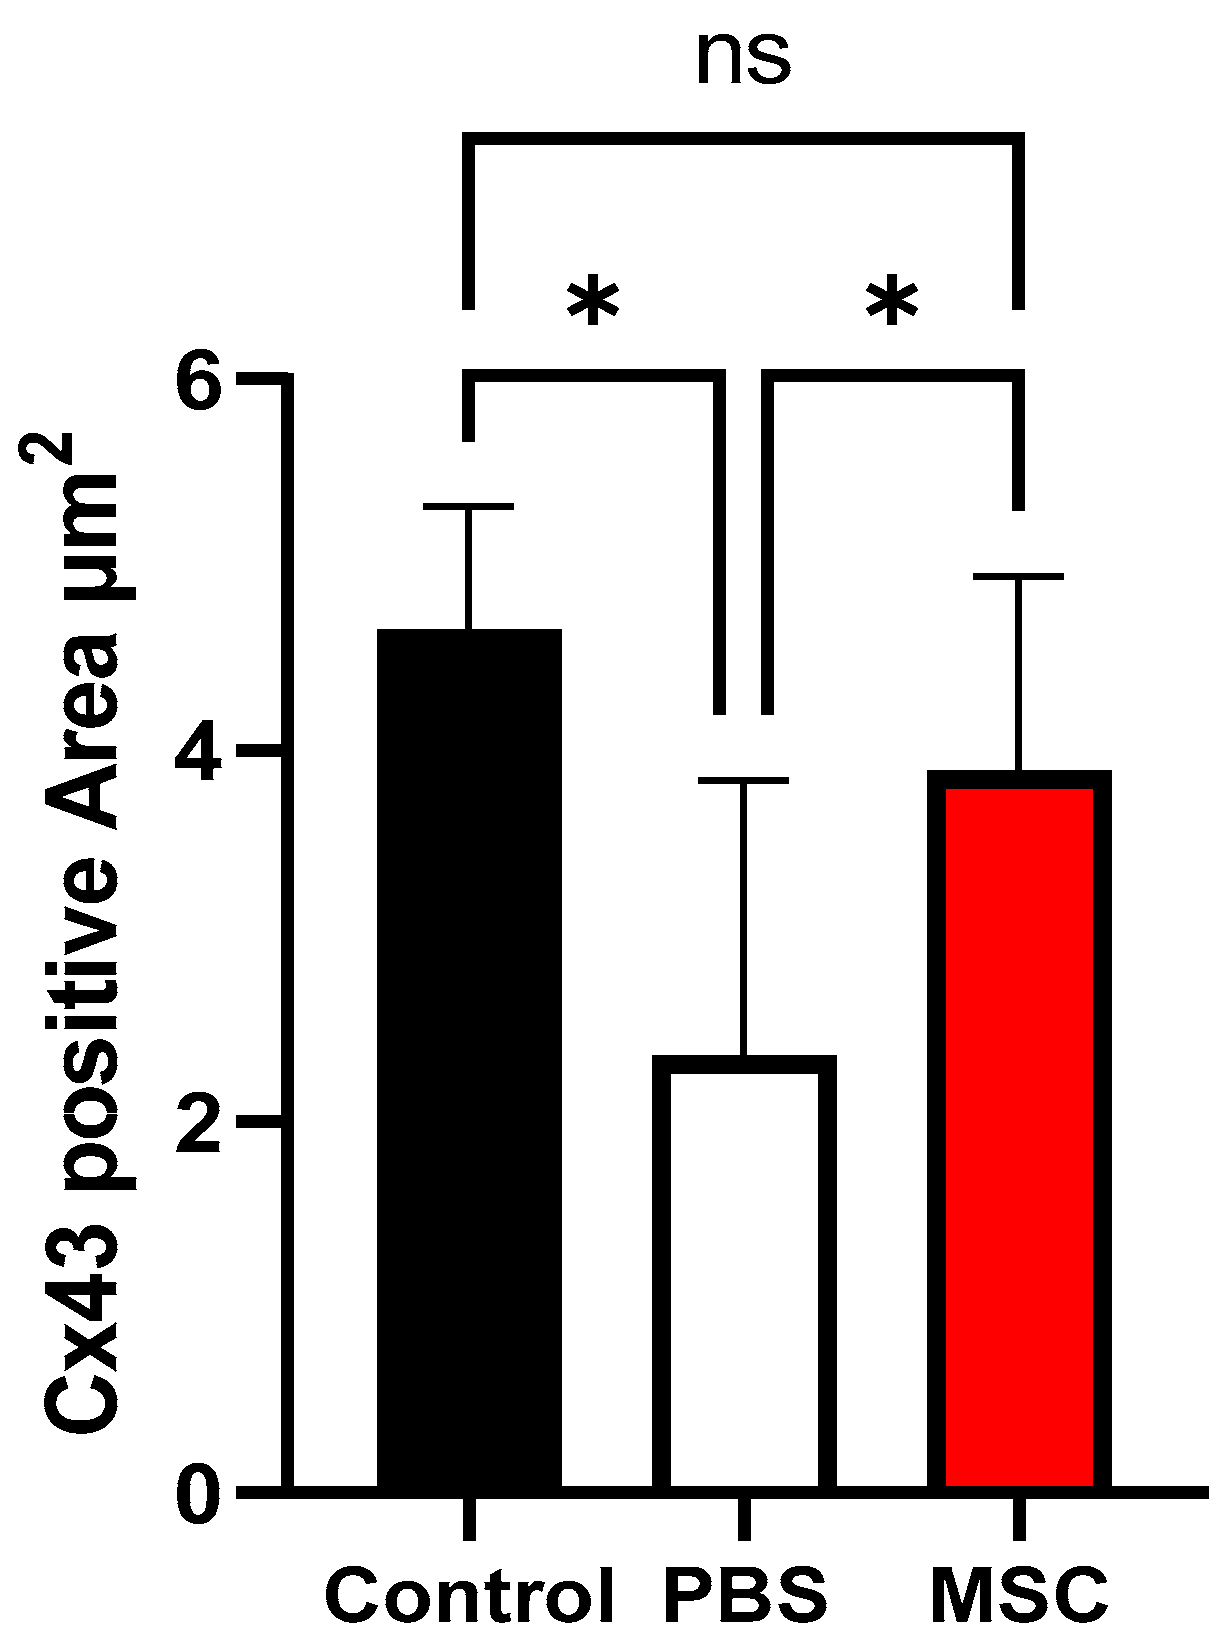

3.3. Histology and Cx43 Expression